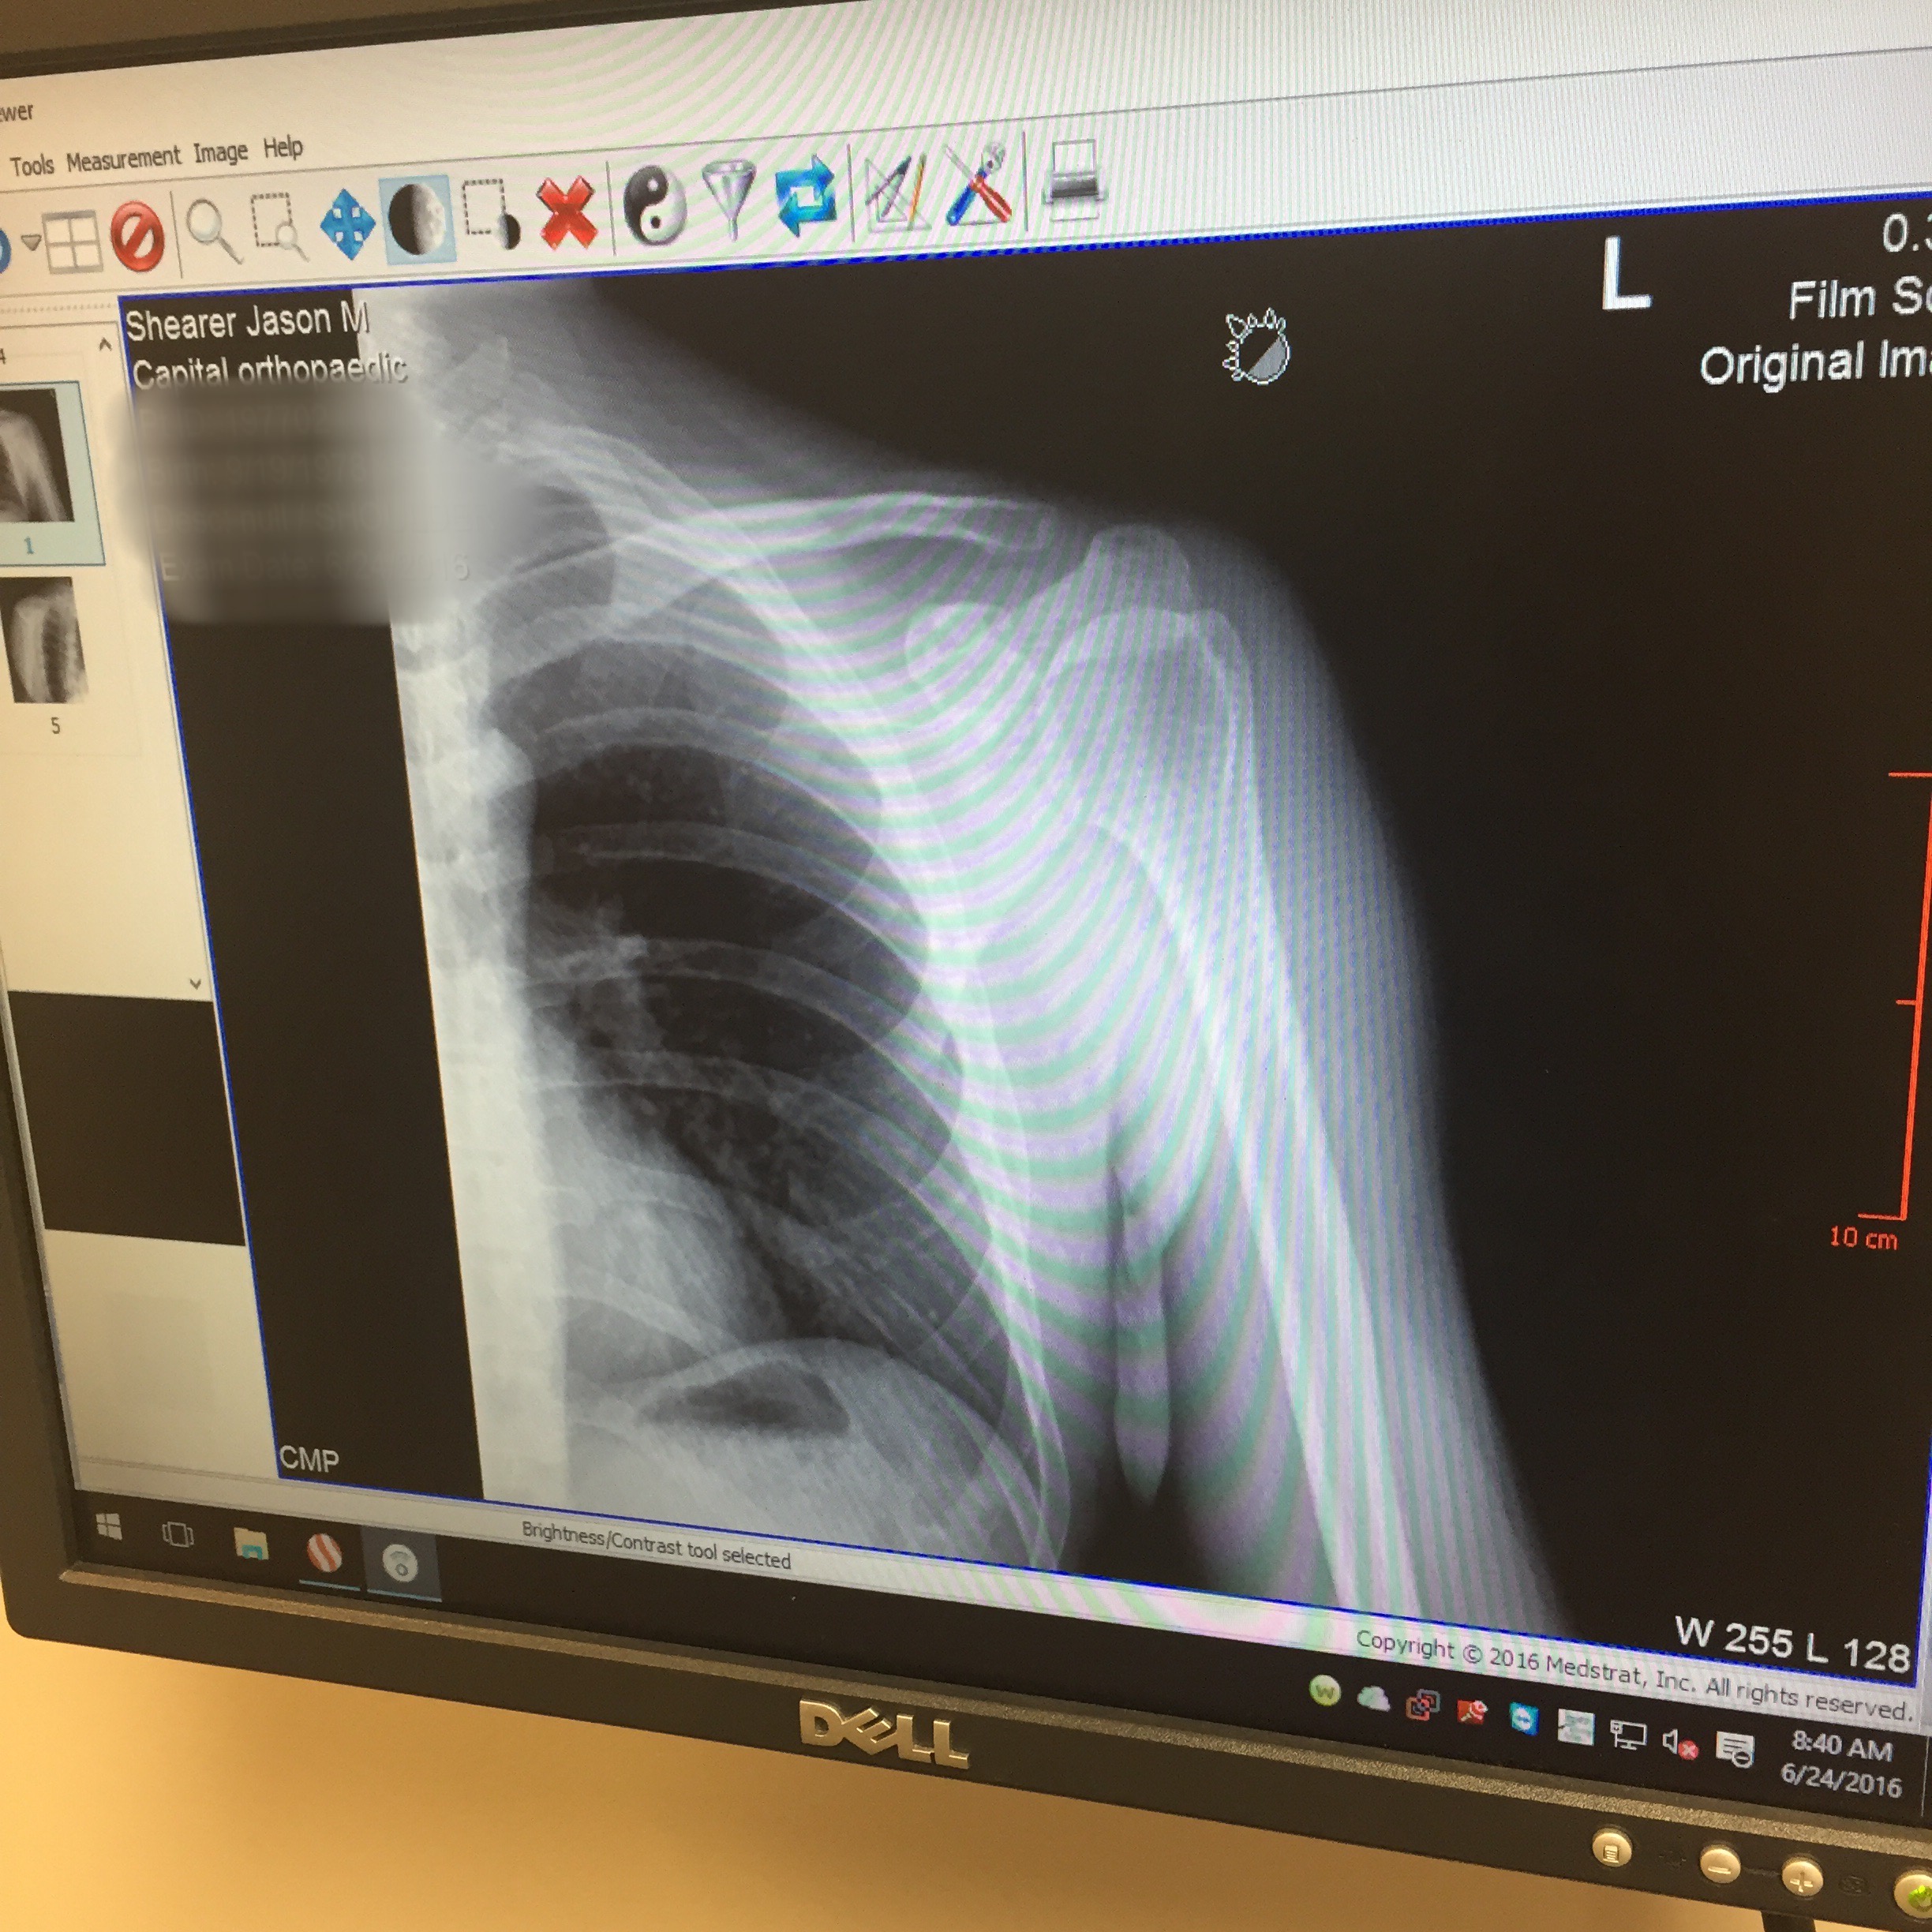

2016 had its highs and lows. If you read my recap of Stagecoach 400 you will know that I was riding a big wave into preparations for Dirty Kanza. That all came to a screeching halt when I was struck by a truck while out on an early AM training ride in May. Broken scapula and a grade 2 separation wasn't going to leave enough time to heal and get back on the horse for a Kanza start.